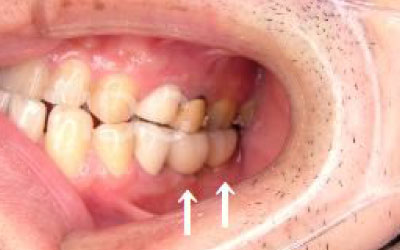

多少の位置のズレであれば、噛み合わせの調整や小さい詰め物で調整することも出来ます。

ただ、抜けてから数年が経って大きく傾いた歯は歯並び矯正をするか、 歯を大きく削ってかぶせ物をする必要があります。

しばらくすると抜けたままでも慣れてきますが、大きな問題が発生します。

2 歯が傾いてくる、落ちてくる

歯の位置は互いに支え合ってバランスを保っています。 つまり、歯が抜けることによって支えが無くなり抜けた部分の両隣の歯が倒れたり、 上の歯が下がってきたりします。